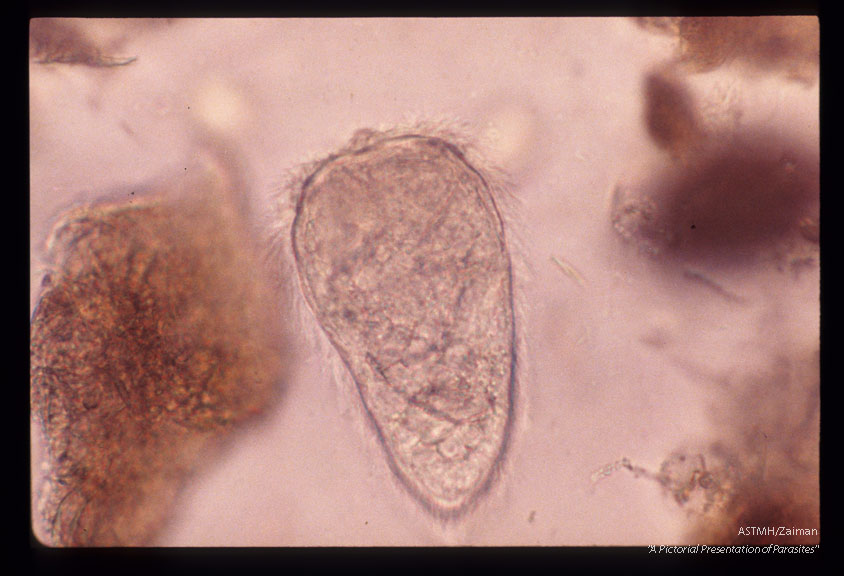

Miracidium.

Schistosoma

Description: Miracidium.